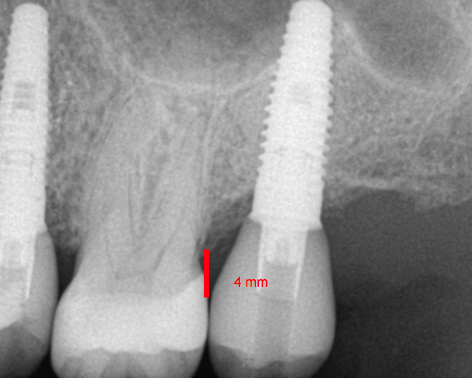

Fig. 1. Occlusal table to platform.

Figure 1